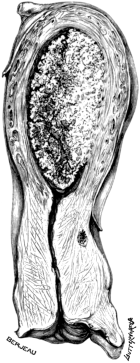

| 242. | Extirpation of the Labyrinth | 425 |